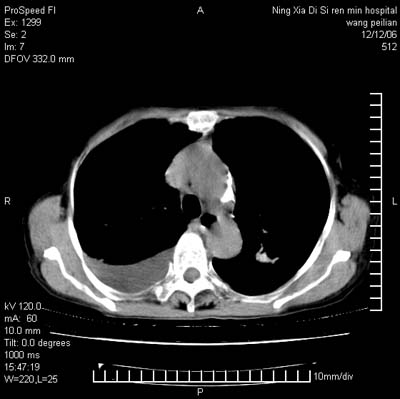

标题: CT5609:胸部:女77 病史不详

两肺可见多个大小不等的结节,左侧有胸水,纵隔淋巴结增大,考虑是细支气管肺泡癌

两肺尖纤维索状影,两下肺结节块状影,且有钙化灶,右胸腔积液。考虑肺结核并胸膜炎。

两肺尖纤维索状影,两下肺结节块状影,且有钙化灶,右胸腔积液。考虑肺结核并胸膜炎肺间质纤维化

考虑:1、慢性支气管炎合并全小叶型肺气肿、间质纤维化;

2、双肺结核;

3、右侧胸膜炎(积液)。

1、双肺继发型肺结核(以纤维、增殖灶为主);

2、右侧胸腔积液;

3、其余符合老年肺改变。

双肺见多个结节状及条索状影,双侧胸腔积液,右侧叶间积液,考虑结核性胸膜炎